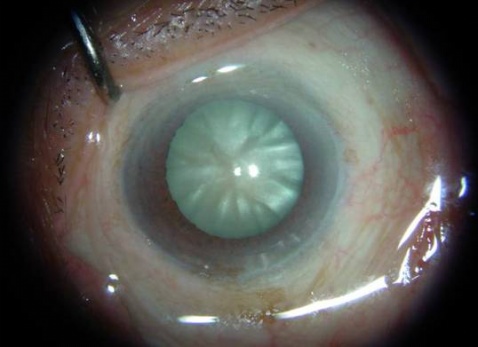

(3)成熟期(mature stage):经膨胀期后,晶状体内水分和分解产物从囊膜逸出,晶状体又恢复到原来体积,前房深度恢复正常。晶状体逐渐全部混浊。患眼视力降至眼前手动或光感。眼底不能窥入。从初发期到成熟期可经10多个月至数10年不等。

(4)过熟期(hypermature stage):如果成熟期持续时间过长,经数年后晶状体内水分继续丢失,体积缩小,囊膜皱缩,出现不规则的白色斑点及胆固醇结晶,前房加深,虹膜震颤。晶状体纤维分解液化,呈乳白色,棕黄色的晶状体核沉于囊袋下方,可随体位变化而移动,上方前房进一步加深,称为Morgagnian白内障。当晶状体核下沉后,视力可突然提高。过熟期白内障囊膜变性,通透性增加或出现细小的破裂。当液化的皮质漏出时,可发生晶状体诱导的葡萄膜炎。长期存在于房水中的晶状体皮质可沉积于前房角;也可被巨噬细胞吞噬,堵塞前房角,引起继发性青光眼,称为晶状体溶解性青光眼。当患眼受到剧烈震动时,可使晶状体囊膜破裂,晶状体核脱入前房或玻璃体内,引起继发性青光眼。过熟期白内障的晶状体悬韧带发生退行性改变,容易发生晶状体脱位。